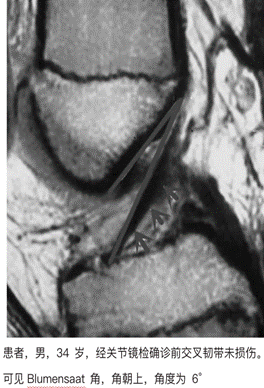

9、Blumensaat 角改变。

Blumensaat 角,即 Blumensaat 线 (股骨髁间窝顶骨皮质线) 和前交叉韧带(ACL)远端部分延长线交叉所形成的夹角。在 MRI 图像的矢状层面上髁间窝部分测得。Blumensaat 角可能相交于膝关节前下方,此时可初步判断前交叉韧带发生了断裂,也可能相交于膝关节后上。有文献研究将相交于膝关节前下方的角度定义为负值,相交于膝关节后上方的度定义为正值。有文献显示当 Blumensaat 角朝后上,>15°时,亦可提升前交叉韧带损伤的概率较大。